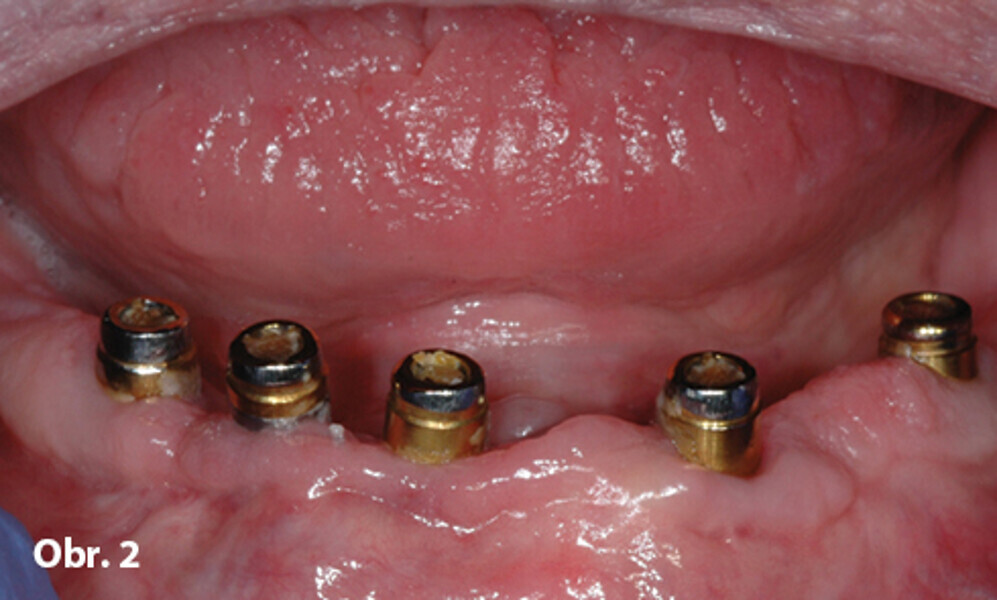

Možnosti ošetření bezzubého oblouku